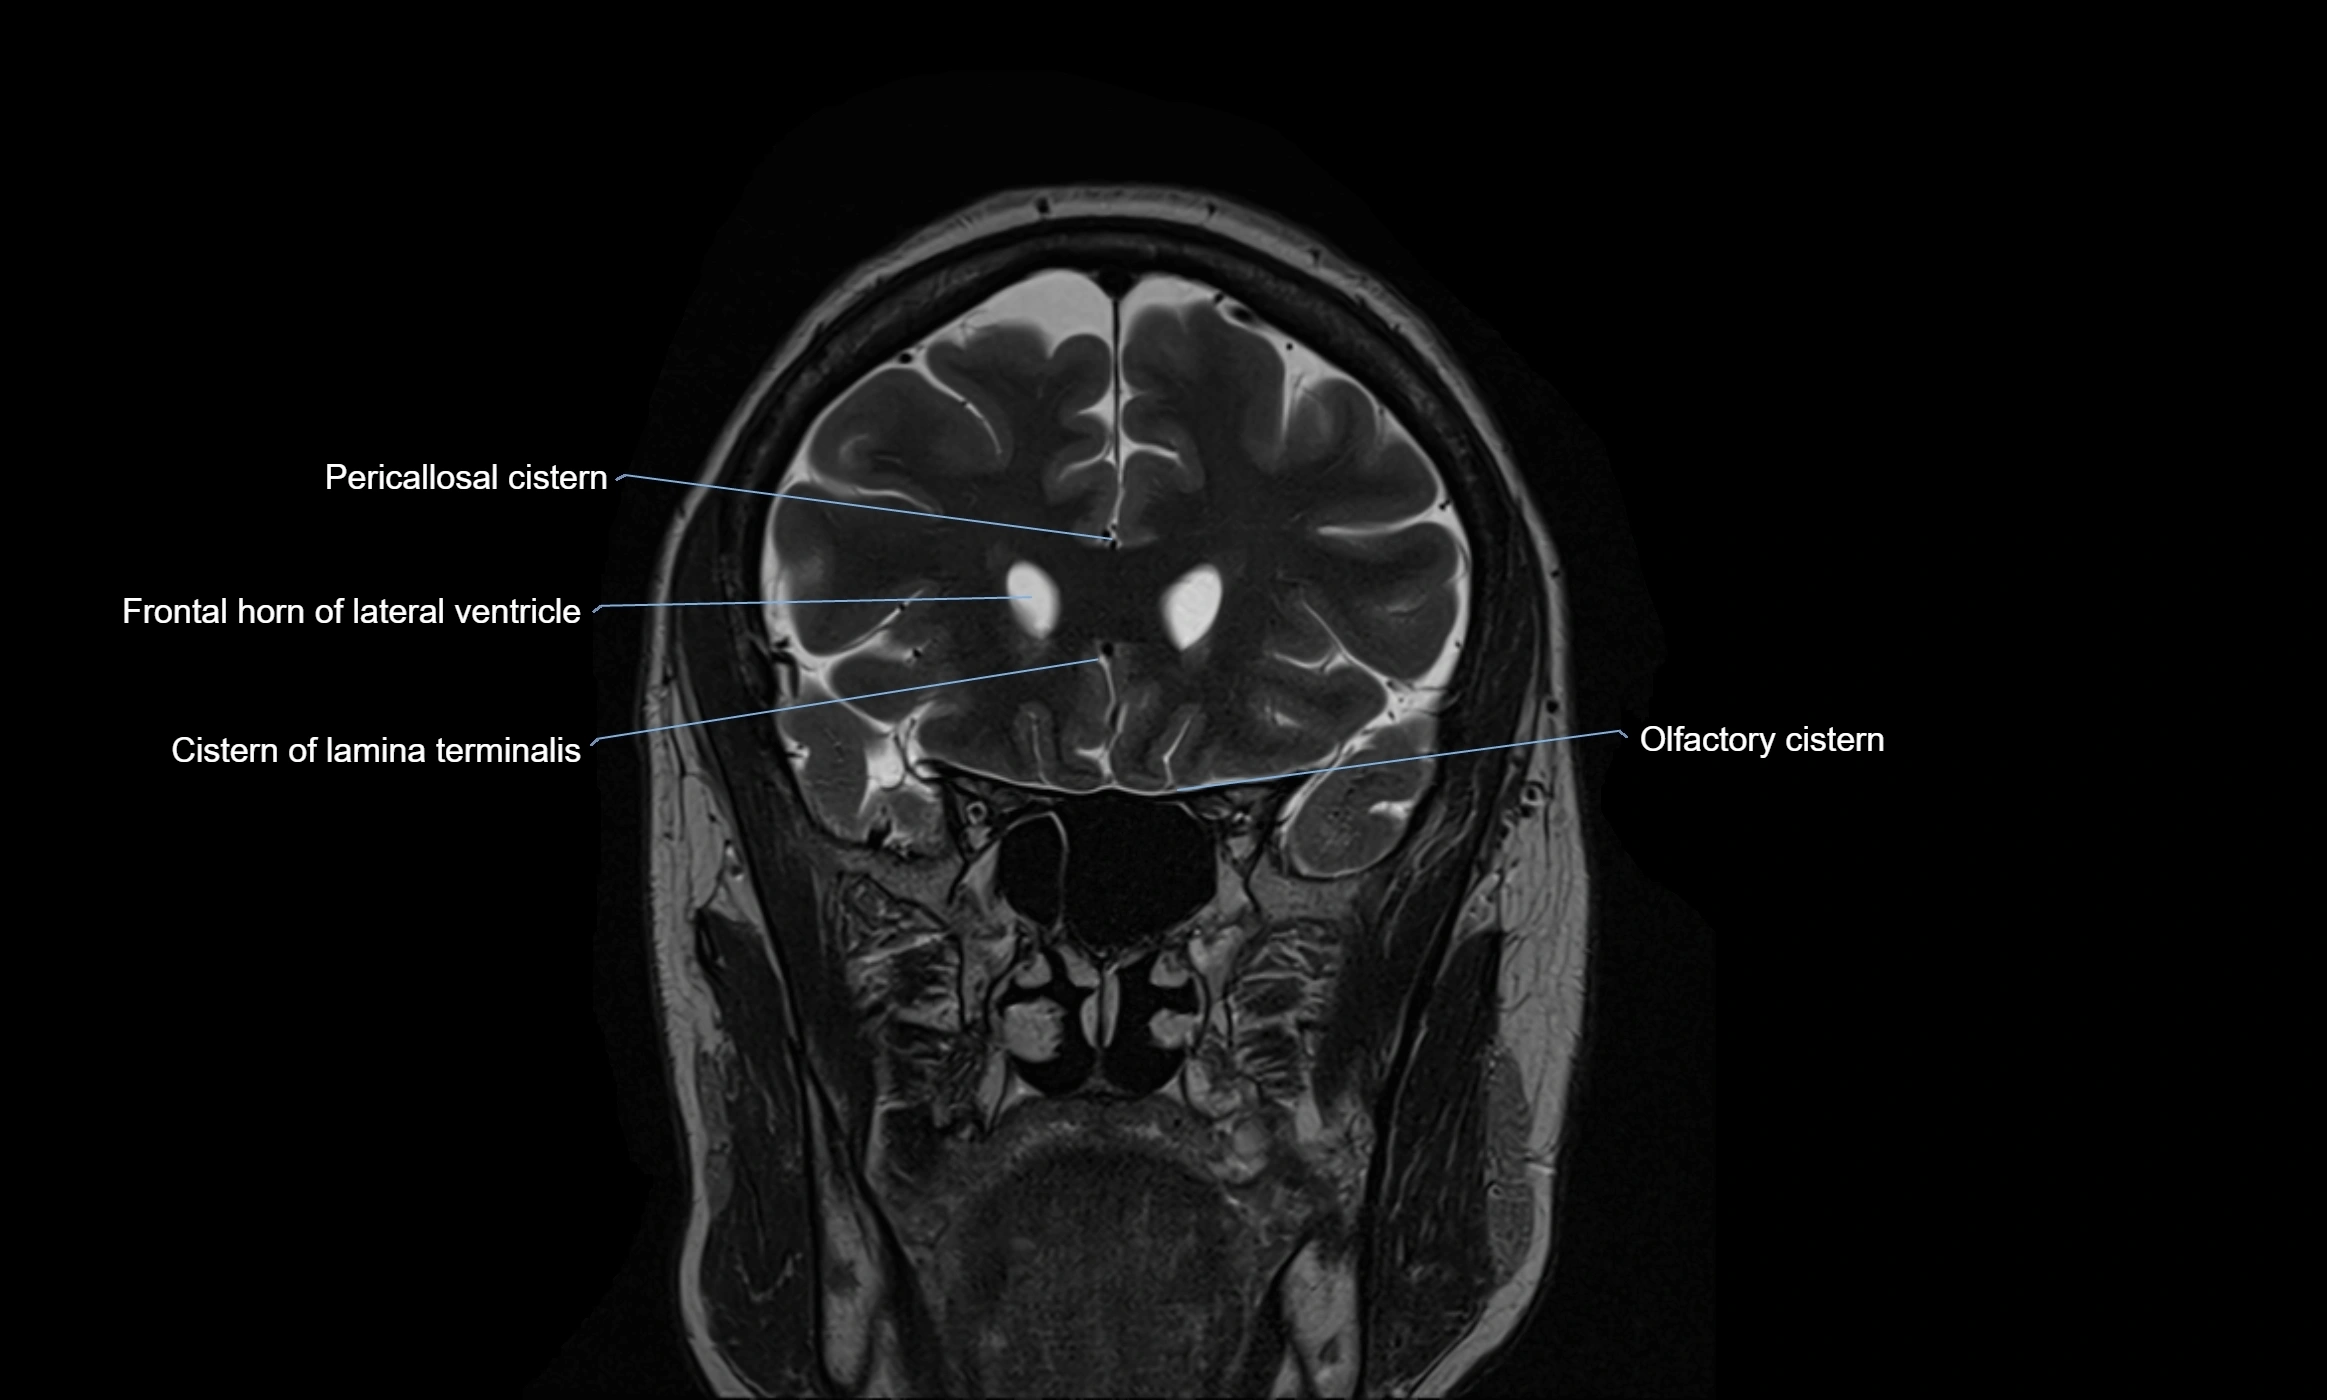

MRI images

image